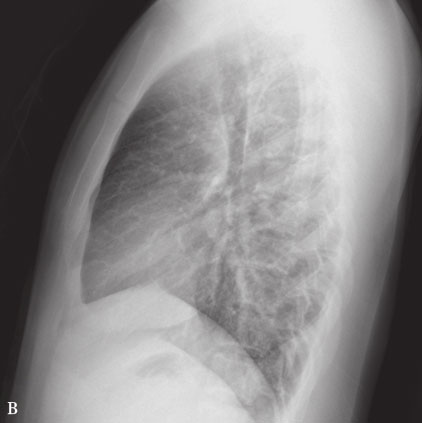

性肺结核的弥漫病灶,多分布于两肺的上中部,大小不一,密度不等,可有融合。儿童急性血行播散性 肺结核有时仅表现为磨玻璃样影,婴幼儿粟粒病灶周围渗出明显,边缘模糊,易于融合。 333 继发性肺结核 继发性肺结核胸部影像表现多样。. 肺结核防治 肺结核(pulmonary tuberculosis PTB)是由结核分枝杆菌引发的肺部感染性疾 病。是严重威胁人类健康的疾病。结核分枝杆菌(简称结核菌,下同)的传染源 主要是排菌的肺结核患者,通过呼吸道传播。. 感染结核菌的人群一生中发生结核 病的概率大约为 10%。 三。肺结核的临床表现 肺结核初期或病变轻微者常无症状或症状轻微,易被病人所忽 略,而一般症状,与许多 其它呼吸道感染相比,除了比较迁延外,一般很少特征性。 (一) 全身症状 1.